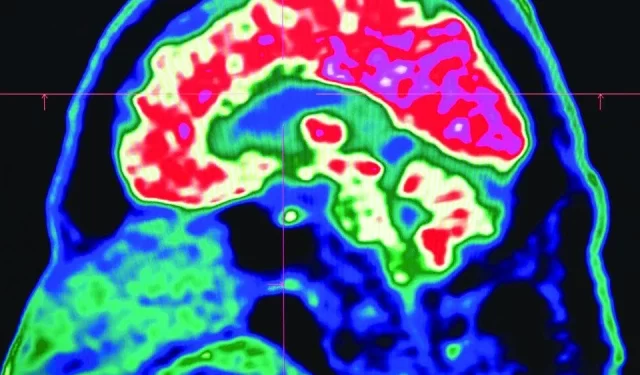

Tiny shards of plastic called microplastics have been detected accumulating in human brains, but there is not yet enough evidence to say whether this is doing us harm, experts have said.

As reported by AFP, these mostly invisible pieces of plastic have been found everywhere from the top of mountains to the bottom of oceans, in the air we breathe and the food we eat. They have also been discovered riddled throughout human bodies, inside lungs, hearts, placentas and even crossing the blood-brain barrier.

The most prominent study looking at microplastics in brains was published in the journal Nature Medicine in February.

The scientists tested brain tissue from 28 people who died in 2016 and 24 who died last year in the US state of New Mexico, finding that the amount of microplastics in the samples increased over time.

The study made headlines around the world when the lead researcher, US toxicologist Matthew Campen, told the media that they detected the equivalent of a plastic spoon’s worth of microplastics in the brains.

Campen also told Nature that he estimated the researchers could isolate around 10 grammes of plastic from a donated human brain — comparing that amount to an unused crayon.